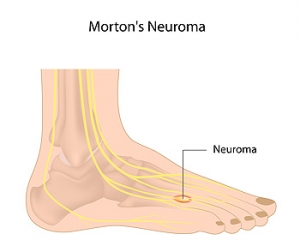

Symptoms of Morton’s Neuroma

The place on the foot where pain from Morton’s neuroma is typically felt is the bottom of the third and fourth toes. This condition can develop as a result of a swollen nerve in the ball of the foot. Some of the symptoms that patients may experience can include numbness or a tingling sensation, a burning pain, or a feeling that something is inside the bottom of the foot. There are, however, some methods that can be implemented which may help in finding mild relief. These may include performing exercises to aid in strengthening and stretching the foot, in addition to massage therapy. Patients may also find comfort in resting the foot, or wearing shoes that have adequate room for the toes to move freely. If you have any kind of pain in your foot, it is suggested that you speak to a podiatrist who can properly diagnose and treat the cause.

The place on the foot where pain from Morton’s neuroma is typically felt is the bottom of the third and fourth toes. This condition can develop as a result of a swollen nerve in the ball of the foot. Some of the symptoms that patients may experience can include numbness or a tingling sensation, a burning pain, or a feeling that something is inside the bottom of the foot. There are, however, some methods that can be implemented which may help in finding mild relief. These may include performing exercises to aid in strengthening and stretching the foot, in addition to massage therapy. Patients may also find comfort in resting the foot, or wearing shoes that have adequate room for the toes to move freely. If you have any kind of pain in your foot, it is suggested that you speak to a podiatrist who can properly diagnose and treat the cause.

Morton’s neuroma is a very uncomfortable condition to live with. If you think you have Morton’s neuroma, contact one of our podiatrists of James Kutchback, DPM, CWS-P. Our doctors will attend to all of your foot care needs and answer any of your related questions.

Morton’s Neuroma

Morton's neuroma is a painful foot condition that commonly affects the areas between the second and third or third and fourth toe, although other areas of the foot are also susceptible. Morton’s neuroma is caused by an inflamed nerve in the foot that is being squeezed and aggravated by surrounding bones.

Morton’s neuroma is a very treatable condition. Orthotics and shoe inserts can often be used to alleviate the pain on the forefront of the feet. In more severe cases, corticosteroids can also be prescribed. In order to figure out the best treatment for your neuroma, it’s recommended to seek the care of a podiatrist who can diagnose your condition and provide different treatment options.

Morton's Neuroma

A neuroma is a thickening of nerve tissue and can develop throughout the body. In the foot, the most common neuroma is a Morton’s neuroma; this typically forms between the third and fourth toes. The thickening of the nerve is typically caused by compression and irritation of the nerve; this thickening can in turn cause enlargement and, in some cases, nerve damage.

Neuromas can be caused by anything that causes compression or irritation of the nerve. A common cause is wearing shoes with tapered toe boxes or high heels that force the toes into the toe boxes. Physical activities that involve repeated pressure to the foot, such as running or basketball, can also create neuromas. Those with foot deformities, such as bunions, hammertoes, or flatfeet, are more likely to develop the condition.

Symptoms of Morton’s neuroma include tingling, burning, numbness, pain, and the feeling that either something is inside the ball of the foot or that something in one’s shoe or sock is bunched up. Symptoms typically begin gradually and can even go away temporarily by removing one’s shoes or massaging the foot. An increase in the intensity of symptoms correlates with the increasing growth of the neuroma.

Treatment for Morton’s neuroma can vary between patients and the severity of the condition. For mild to moderate cases, padding, icing, orthotics, activity modifications, shoe modifications, medications, and injection therapy may be suggested or prescribed. Patients who have not responded successfully to less invasive treatments may require surgery to properly treat their condition. The severity of your condition will determine the procedure performed and the length of recovery afterwards.